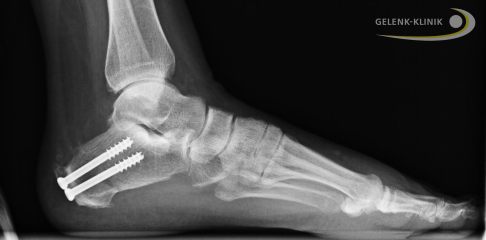

Die Keilentfernung korrigiert die Stellung des Fußes insgesamt und führt zur Druckentlastung am Achillessehnenansatz. Die Position wird mit Schrauben fixiert. © Dr. med. Thomas Schneider

Röntgenbild nach Umstellungsoperation: Bis zur kompletten Ausheilung wird die korrigierte Position des Fersenbeins mit Schrauben fixiert. © Dr. med. Thomas Schneider